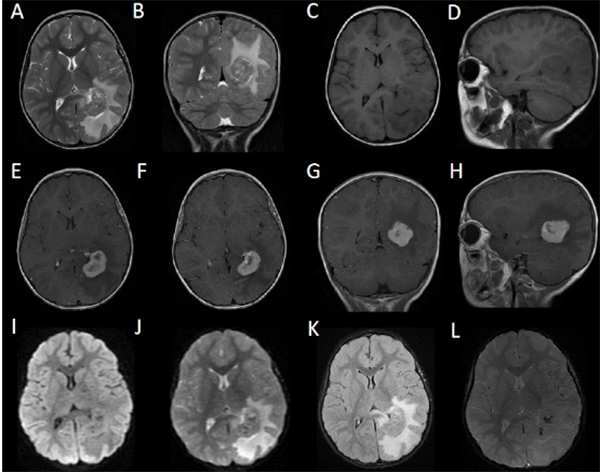

El informe histopatológico fue compatible con Schwannoma (Figura 2).

Figura 2: Cortes histológicos de la pieza. Se observan células bipolares ausadas con bajo índice de mitosis. Alternan areas de gran densidad neuronal (Antoni tipo A) con otras de baja (Antoni Tipo B).

Tras 3 años de seguimiento, la paciente se encuentra sin déficit neurológico, libre de crisis y sin requerimiento de medicación antiepiléptica. El estudio control actual de RMN no evidencia residuo tumoral (Figura 3).

Figura 3: Control posoperatorio: exéresis completa.